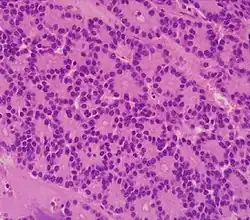

| Pancreatic neuroendocrine tumor | 5% | Multiple nests of tumor cells | ![]() |

||